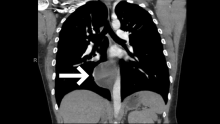

This is a case of a twenty-nine-year-old woman who initially presented to the emergency department with right-sided pleuritic chest pain, syncope, and leukocytosis. A CT angiogram revealed bilateral segmental and subsegmental lower lobe pulmonary emboli, as well as an indeterminate round posterior mediastinal mass measuring approximately 6 cm in its largest diameter and located just right of the midline, adjacent to the esophagus. The patient was scheduled for a right-sided video-assisted thoracoscopic surgery (VATS) for resection of the posterior mediastinal mass vs. cyst after three months of anticoagulation was completed for the treatment of her pulmonary emboli.

The patient was positioned with her right side up in the left lateral decubitus position and a single 10 mm camera port was placed in the anterior axillary line over the seventh rib. Three other 5 mm ports were placed, one in the eighth intercostal space (ICS) midaxillary line, one in the ninth ICS posterior axillary line, and one in the sixth ICS posterior axillary line. Upon entering the thoracic cavity, the 6 cm cystic structure was visualized in the posterior mediastinum, located within the inferior pulmonary ligament and adjacent to the inferior pulmonary vein and esophagus. The patient was found to have several lung adhesions secondary to prior infections associated with the cyst. These adhesions were taken down with a Ligasure device.

The excision of the cyst began with resection off the inferior pulmonary ligament and the right lower lobe of the lung. The cyst was then drained, revealing the purulent contents. The empty cyst was then resected off the esophagus. The cyst was then completely excised from the inferior pulmonary ligament and the inferior pulmonary vein. Complete resection of the cyst is essential to prevent recurrence.